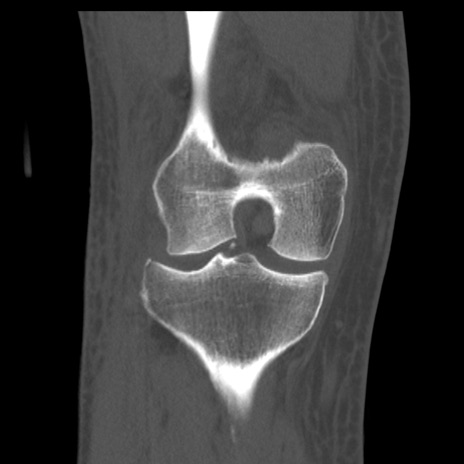

症例28 右膝関節CT(冠状断像)

右膝関節CT